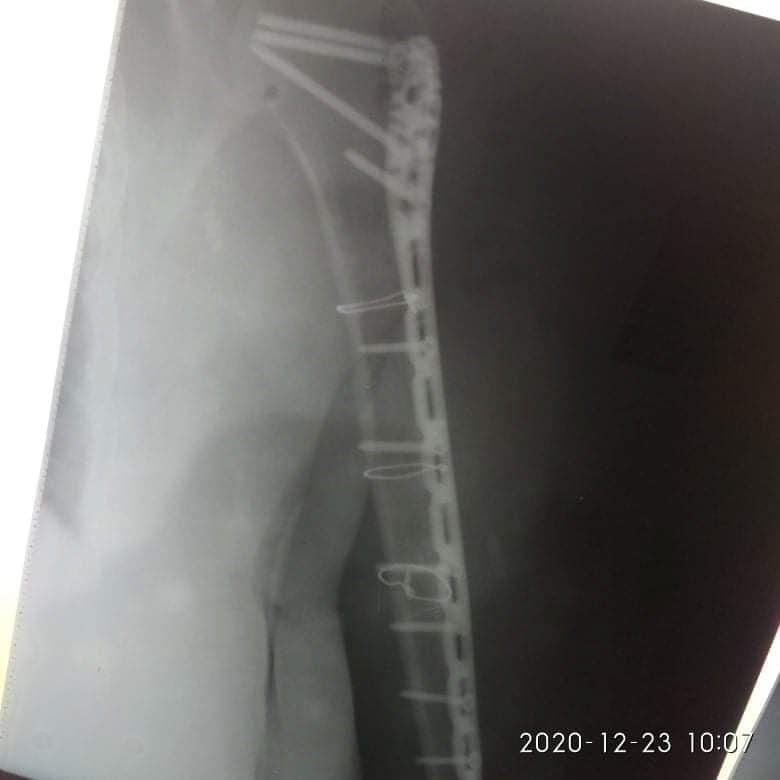

Діагноз: Закритий багатовідламковий перелом діафізу правої плечової кістки", - йдеться в дописі.

21 грудня їй провели 4-ьох годинну операцію - остеометалосинтез правої плечової кістки за допомогою LCP проксимальної Philos пластини та гвинтів.